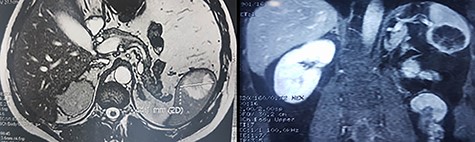

We report the case of 47-year-old men, with a chronic renal failure, who had been operated on 3 years previously for a total left radical nephrectomy for clear cell renal cancer of stage pT3G1N0M0. During the follow-up of the patient, a routine cancer screening with ultrasound revealed a mass in the spleen of about 4 cm of diameter. Laboratory investigations were normal apart from known renal failure (Table 1). Due to known chronic kidney disease and allergy to Iodinated contrast media, an abdominal magnetic resonance imaging (MRI) confirmed the presence of a splenic lesion (Fig. 1). Based on these radiological findings, the splenic mass was diagnosed as a suspicious metastatic lesion. An open splenectomy was performed. The patient recovered uneventfully and was discharged 5 days after surgery. He received pneumococcal, meningococcal and Haemophilus influenzae vaccine. Histologic analysis of the lesion confirmed the presence of clear cell renal cancer metastasis (Fig. 2). The patient was referred to the oncology department for adjuvant treatment with sunitinib. His follow up consisted on abdominal ultrascan (US) every 3 months and MRI at 6 and 12 months from surgery. After 36 months, the patient is doing well with no signs of tumor recurrence.